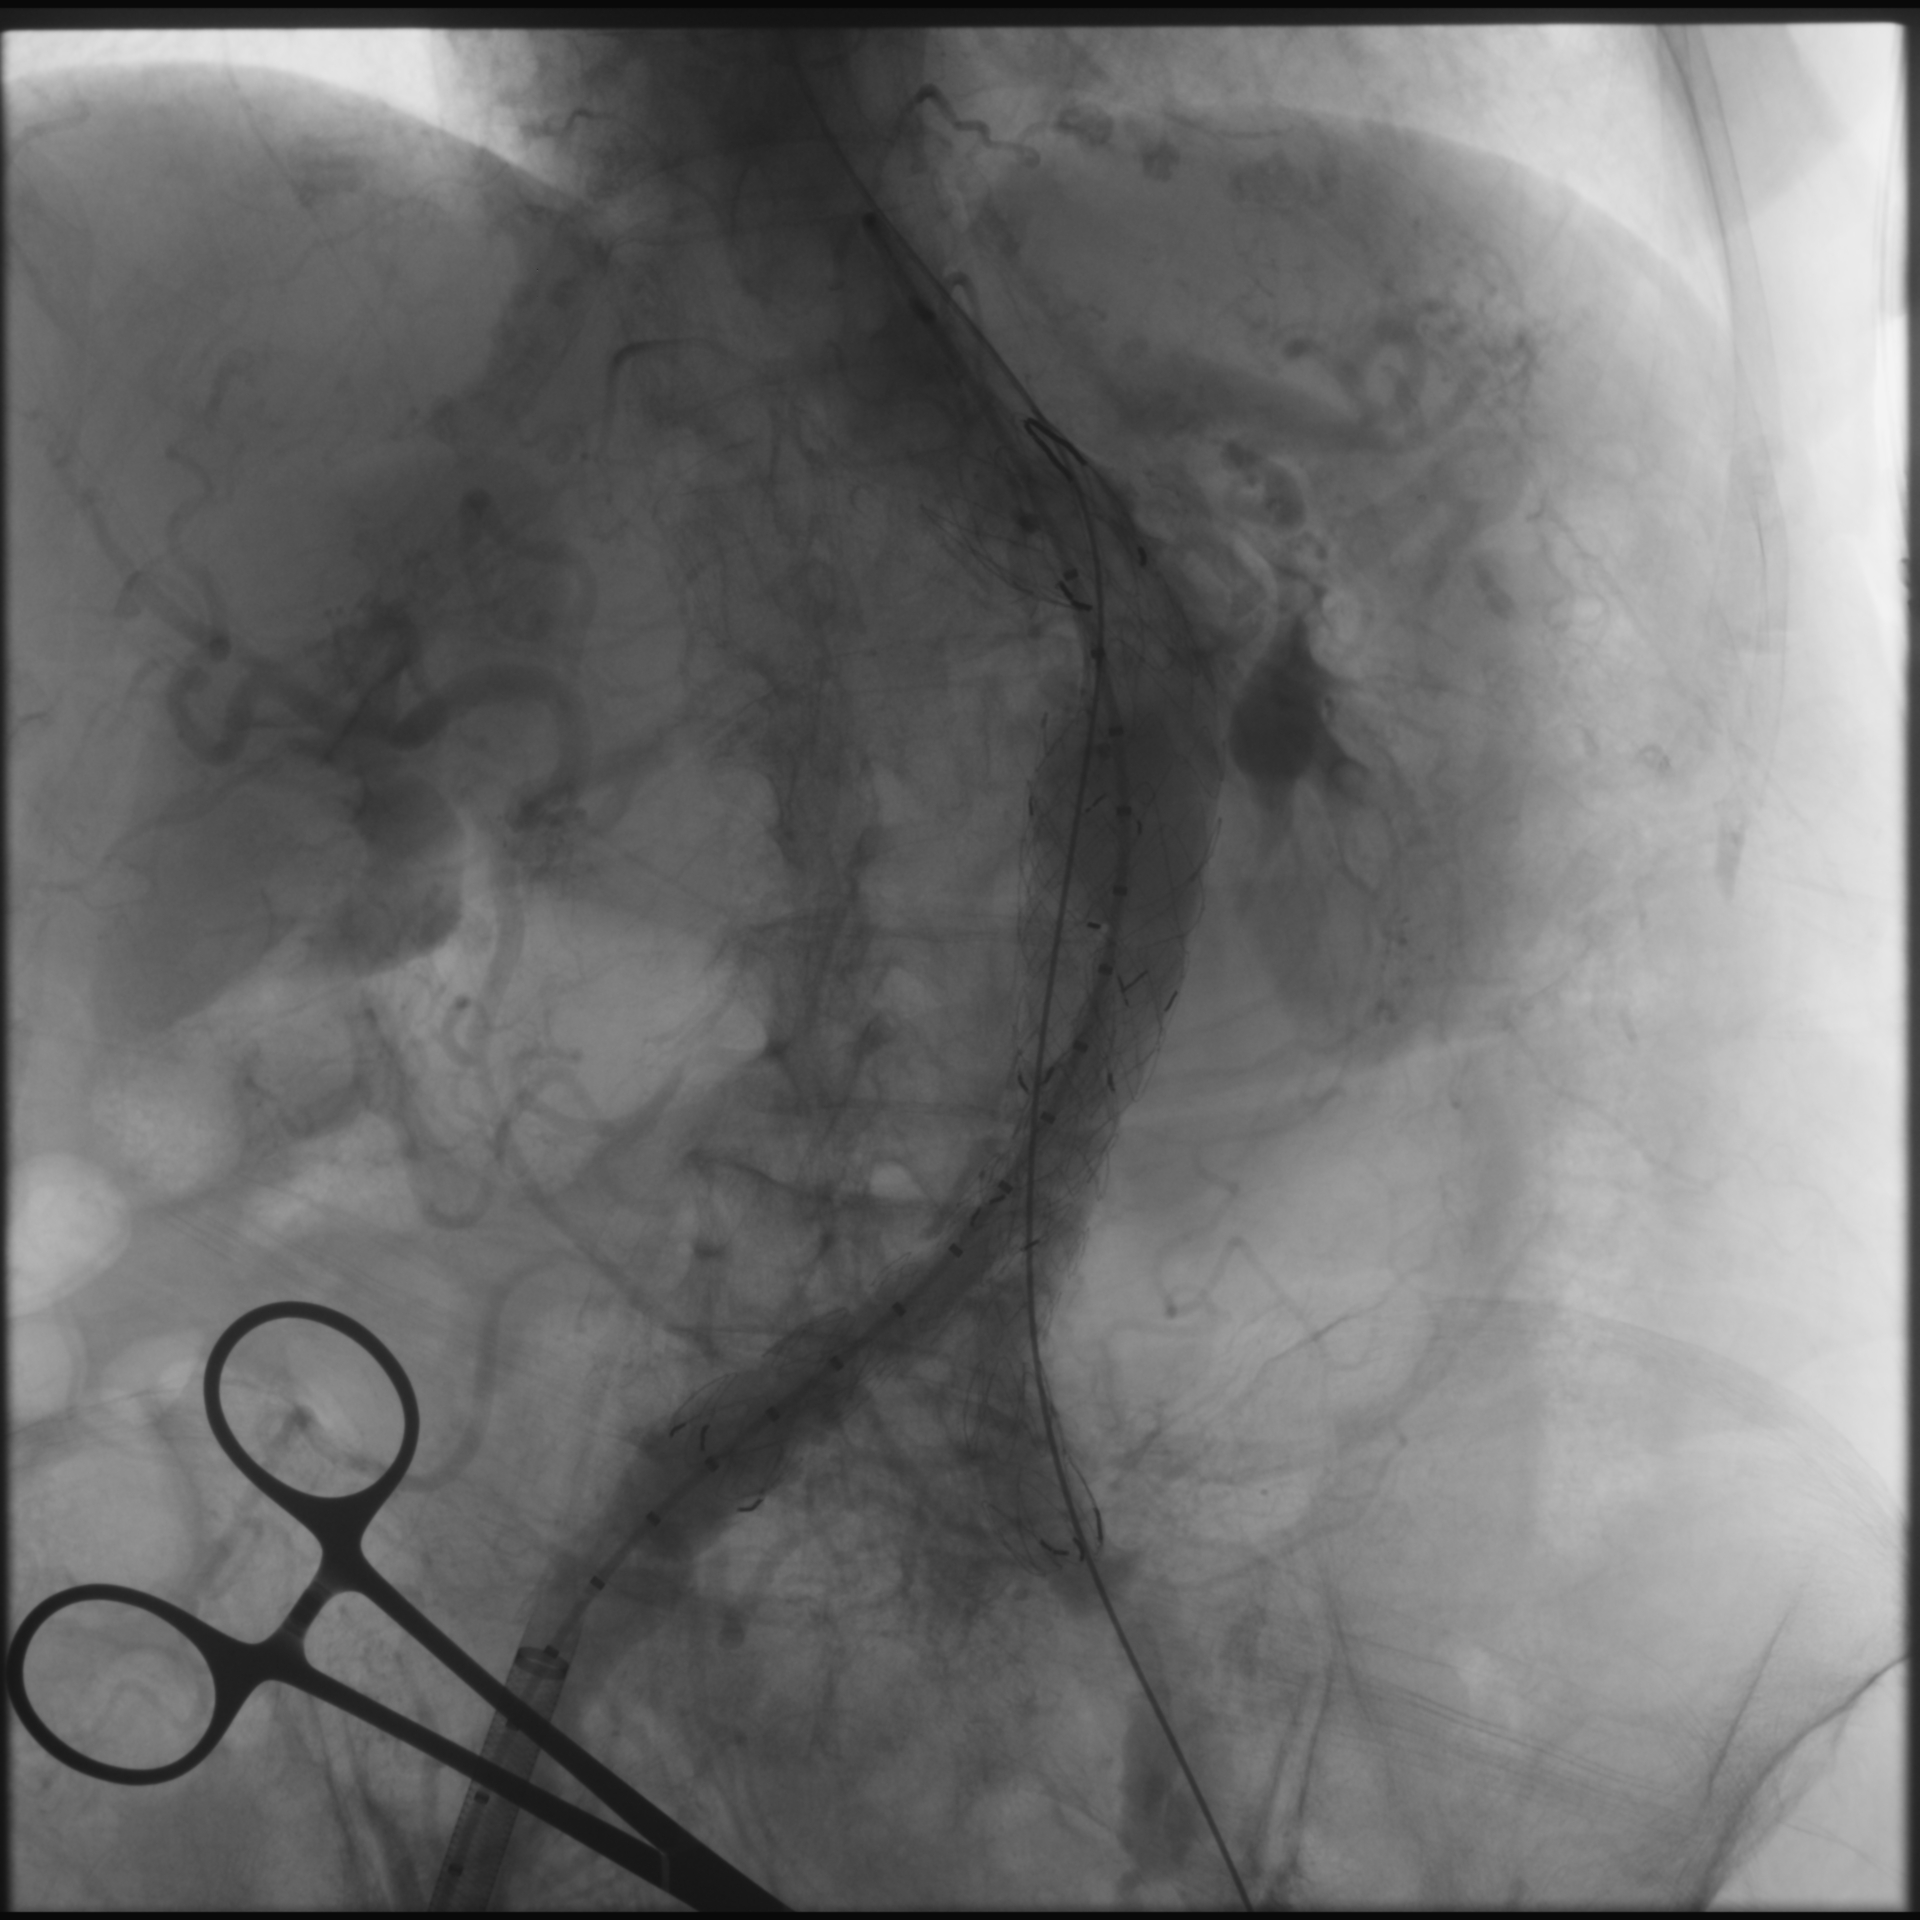

Percutaneous transluminal angioplasty (POBA) was performed on the proximal left common iliac artery using a 10 ¡¿ 80 mm Mustang balloon (Boston Scientific, USA) inflated and showing a balloon-waist formation consistent with a tight, fibrotic lesion. After gradual dilation up to 6 atm, the waist resolved and the lumen expanded, allowing smooth wire and sheath passage. The SEAL NOVUS stent-graft system (S&G Biotech, Korea) was used, with the main body (24 ¡¿ 50 mm) introduced via the right common femoral artery. Two flared iliac limbs, 12(18) ¡¿ 100 mm on the left and 12(16) ¡¿ 80 mm on the right, were deployed in a ballerina (crossed-limb) configuration to accommodate left-sided tortuosity and prevent kinking. During contralateral limb cannulation, angiography was performed within the main body to confirm the wire course inside the graft before advancing the sheath. Completion angiography demonstrated a Type Ia endoleak, treated with proximal neck flaring using a Coda LP balloon (Cook Medical, USA) under a rapid inflation–deflation technique to optimize sealing and prevent graft migration. Final angiography showed excellent proximal seal and bilateral flow, and follow-up CTA confirmed durable aneurysm exclusion without endoleak.